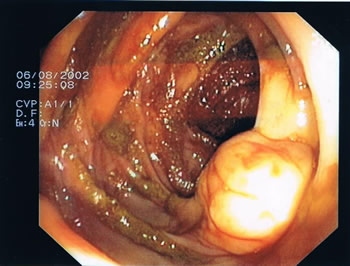

Endoskopische Bilder. Das Darmlumen innerhalb der einzelnen Darmabschnitte kann eher rundlich, leicht eingeengt oder dreieckförmig aussehen, entsprechend des anatomischen Aufbaus (s. Abb.1-4). Grundsätzlich gibt es verschiedene Arten von Polypen mit unterschiedlichen Konfigurationen und von verschiedener Größe. Kugelig(Abb.6) mit schmaler Verbindung zur Darmwand, hügelig mit breiter Basis, muschelförmig, die sich häufig an eine Querfalte anschmiegen, gestielte Polypen, die über einen Stiel mit der Darmwand verwachsen sind und sessile Polypen (Abb.5), die breitbasig auf der Darmwand aufsitzen. Der Übergang zum Dünndarm (Ileocaecal-Klappe) kann des Öfteren ein polypöses Aussehen vortäuschen (Abb.4).